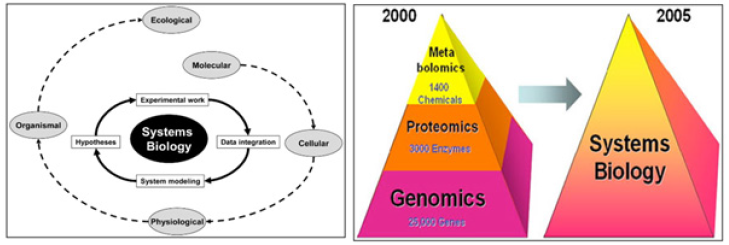

The core information resources of systems biology are the “omics” sciences (Figure 2A, B).

Figure 2A & 2B: Systems Biology. Systems biology incorporates the whole workflow from experimental design and data management through data acquisition, pro-cessing and modelling to visualization and interpretation of the experimental findings. The goal of systems biology is to discover new emergent properties to better understand the entirety of processes that happen in a biological system. Some of the areas of study are listed below, along with the associated OMICS-technologies being integrated into OMICS portfolio.